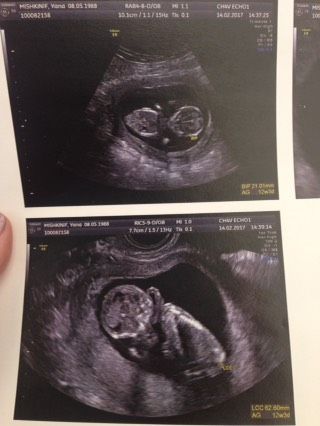

Ну вот и моя очередь пришла говорить о первом УЗИ :) врачи во Франции не многословны конечно… все к вас хорошо, держите бумаги и до свидания ? по бумагам тоже просмотрела- все хорошо. Смотрели и по животу, и палочкой. Вообще не больно и аккуратно! Я уже настроилась, что на живот давить сильно будут… дальше сдала кровь сразу и записалась на роды в роддом :) вот. Очень рады))) муж со мной был, смотрел, как танцует наш малыш.

Поздравляю! А мне перенесли на пятницу ((( Странно, а мы почти час сидели, пока он пытался измерить толщину nuque… потом полчаса пытались пол разглядеть, короче веселый мужик нам попался. Про запись на роды мне ничего не говорили, а че будет, если не запишешься?)) на улице рожать ?

У вас случайно обвития нет пуповины на нижнем фото?

Я тоже на это обратила внимание.

Врач ничего не сказал… да р мы рассматривали другие фото, там тоже не видно.